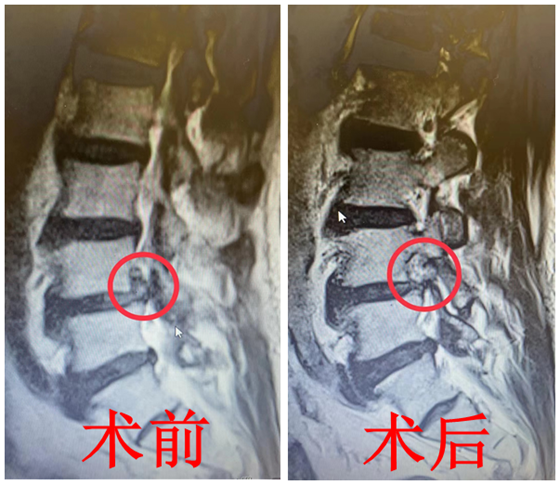

入院后,骨科负责人陈芳田主任医师及其团队再次了解患者病情,并为其进行详细体查,发现患者膝关节处并无异常,但轻微触摸膝关节上方的皮肤后,会感到疼痛加重。经验丰富的骨科医师团队立刻意识到可能是腰椎出了问题,立即安排其进行腰椎影像学检查。经过全面评估,最终患者被确诊为“腰椎间盘突出症”。

针对金叔叔病情,骨科团队经过详细的术前讨论,完善术前准备后,陈芳田主任医师带领团队为其在局麻下实施经皮微创椎间孔镜腰椎间盘突出症髓核摘除手术,直接解除神经压迫,患者左膝疼痛即刻缓解,当晚睡了个好觉。